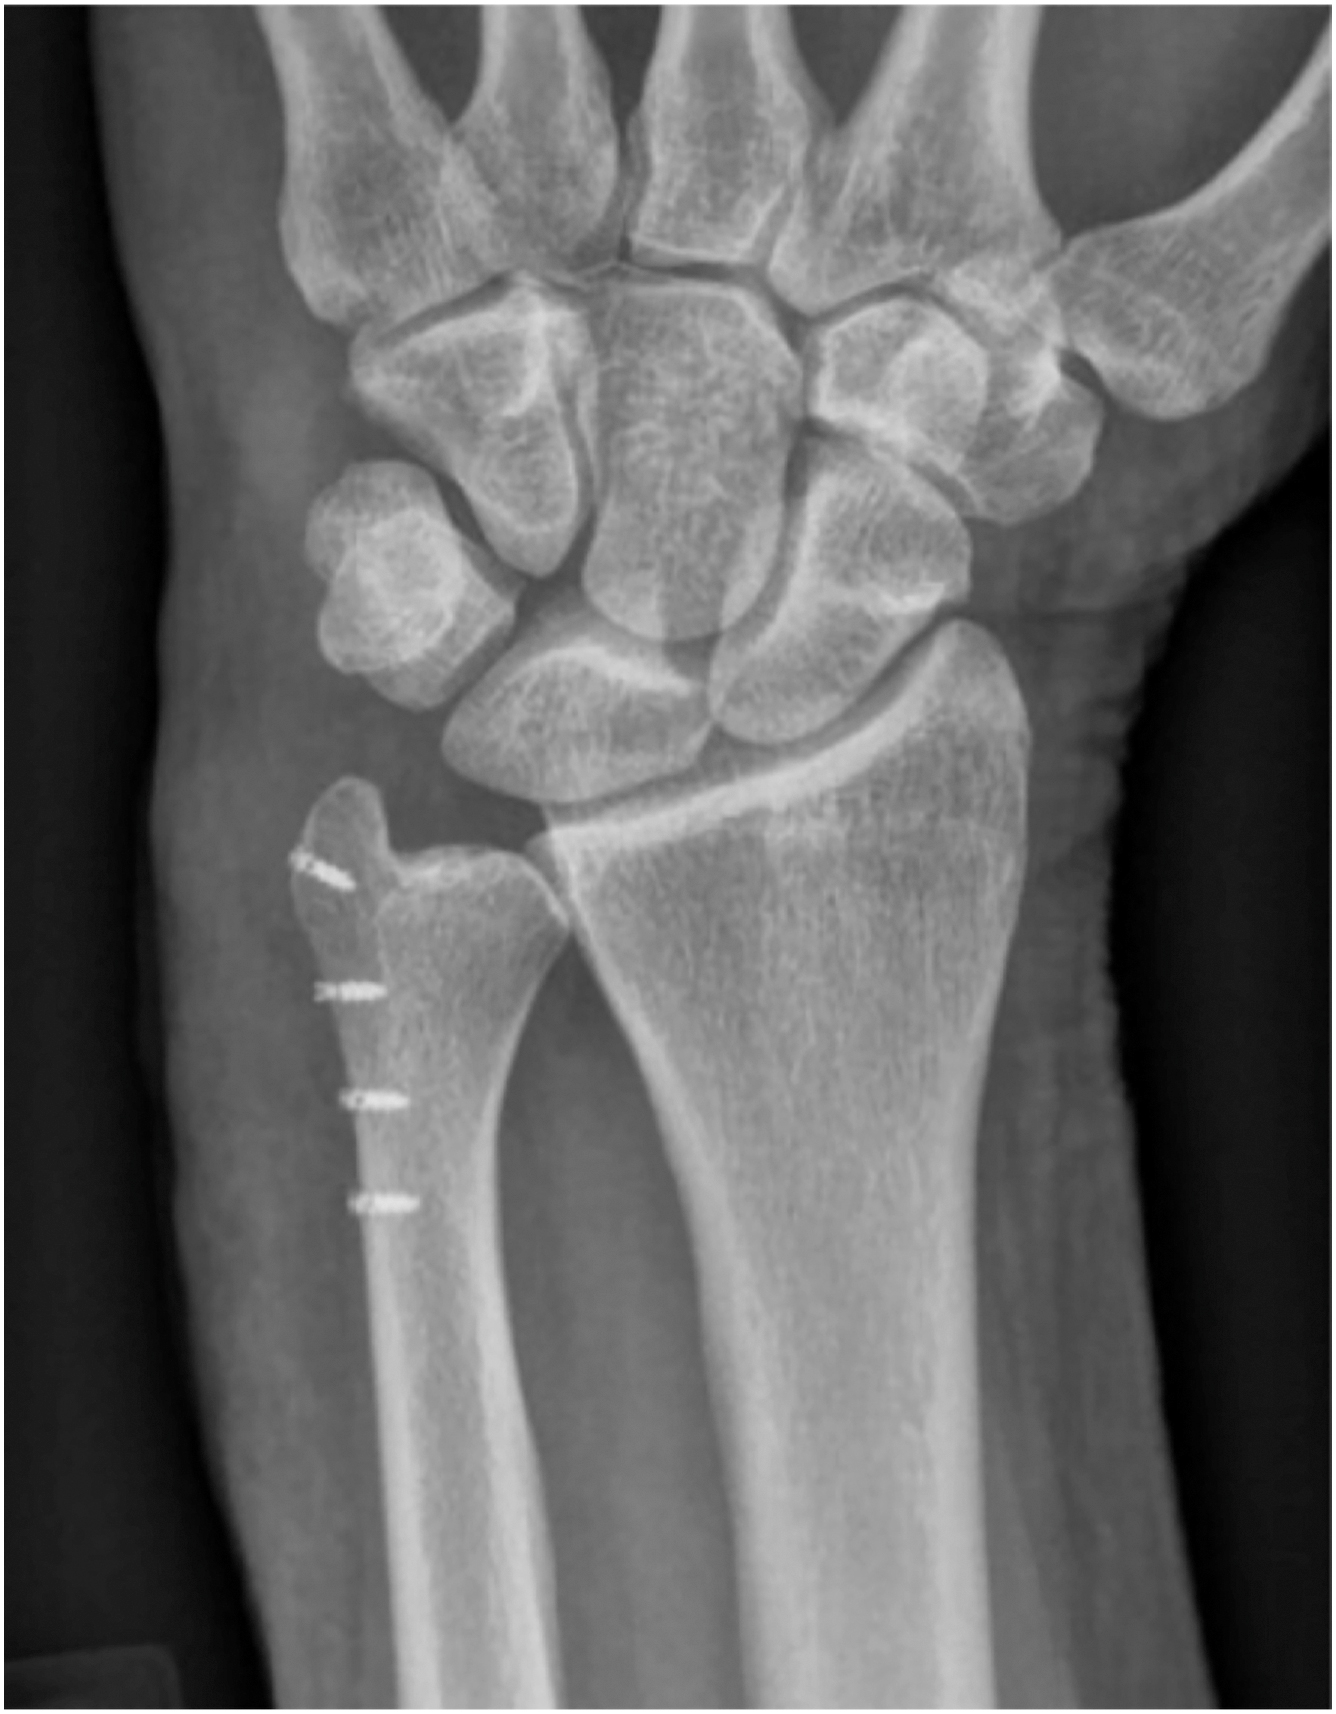

Numerous treatment options for SLIL injuries have been described and are guided by the degree (partial vs complete) and chronicity of injury. Partial tears are initially treated with a period of immobilization, anti-inflammatory medications, and/or cortisone injections. Those who continue to have symptoms may undergo arthroscopic evaluation with possible debridement and thermal shrinkage. For complete tears, open repair or reconstruction may be considered. Though many techniques for this have been described, our preference is internal brace reconstruction with dorsal capsulodesis ( Figs. 3 and 4 A, B ).

Postoperatively, athletes who undergo SLIL reconstruction with capsulodesis are immobilized for 4 weeks in a molded wrist brace with the thumb and fingers free. Range of motion is initiated at 4 weeks and strengthening is initiated at 6 weeks postoperatively. Sport-specific activities begin at 12 weeks postoperatively with the goal of return to play at 4 to 6 months.